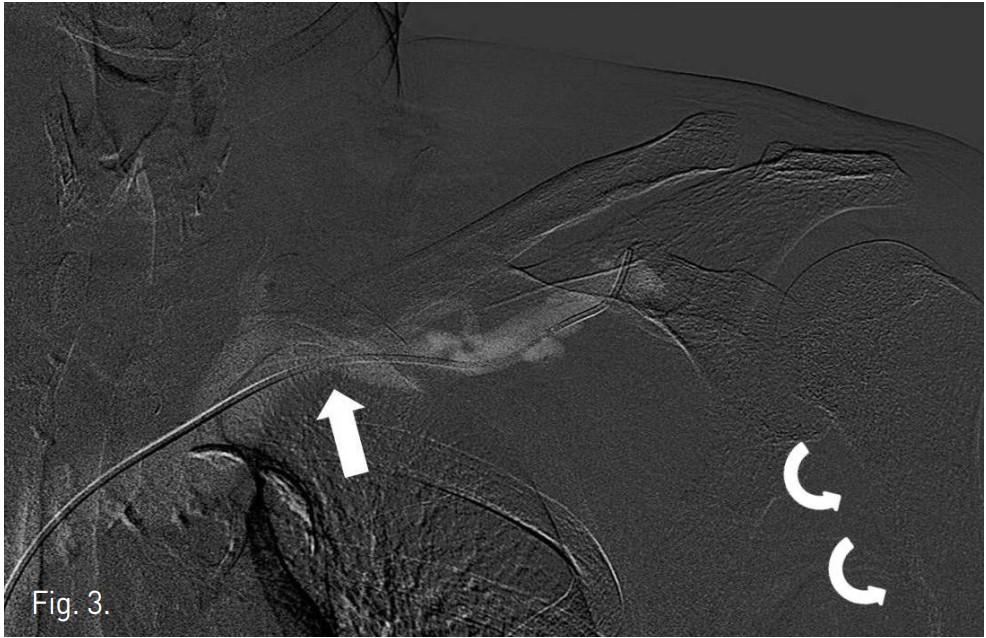

Right common femoral vein을 통해 left subclavian vein에 5F Cobra catheter (Cook, Bloomington, U.S.A)를 위치시킨 후, 시행한 venogram에서 subclavian vein의 total occlusion이 관찰되었다. 팔을 올리고 시행한 venogram에서 막힌 subclavian vein이 stenotic lesion으로 관찰되고 distal portion이 조영되었다. Guide wire로 stenotic lesion을 통과한 후 12mm-6cm balloon catheter (Ultra-thin, Boston scientific, USA)를 이용하여 stenotic lesion에 balloon angioplasty를 시행하였으나, 팔을 내리면 다시 stenosis가 심해져서 추가로 수 차례 balloon angioplasty를 시행하였다. 시술 후 팔을 내리고 시행한 follow up venogram에서 stenotic lesion이 호전되었다(Fig. 3).

Fig. 3.

Fig. 3. After angioplasty, subclavian venogram with the arms held to the sides shows improved occlusion of subclavian vein.